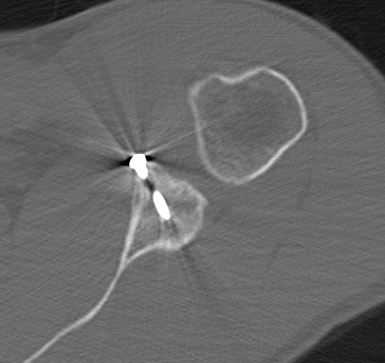

Bone block positioning

- coracoid must not overhang medial to avoid osteoarthritis

- coracoid < 5 mm medial to glenoid rim

- coracoid lower half of glenoid 2 - 5 o'clock

- fixation screws purchases posterior glenoid cortex

- screws do not penetrate articular surface

Hardware issues

Screw backout

Intra-articular screw

Graft malposition

Screws and graft too medial

Bone graft too medial

Coracoid graft too superior on glenoid